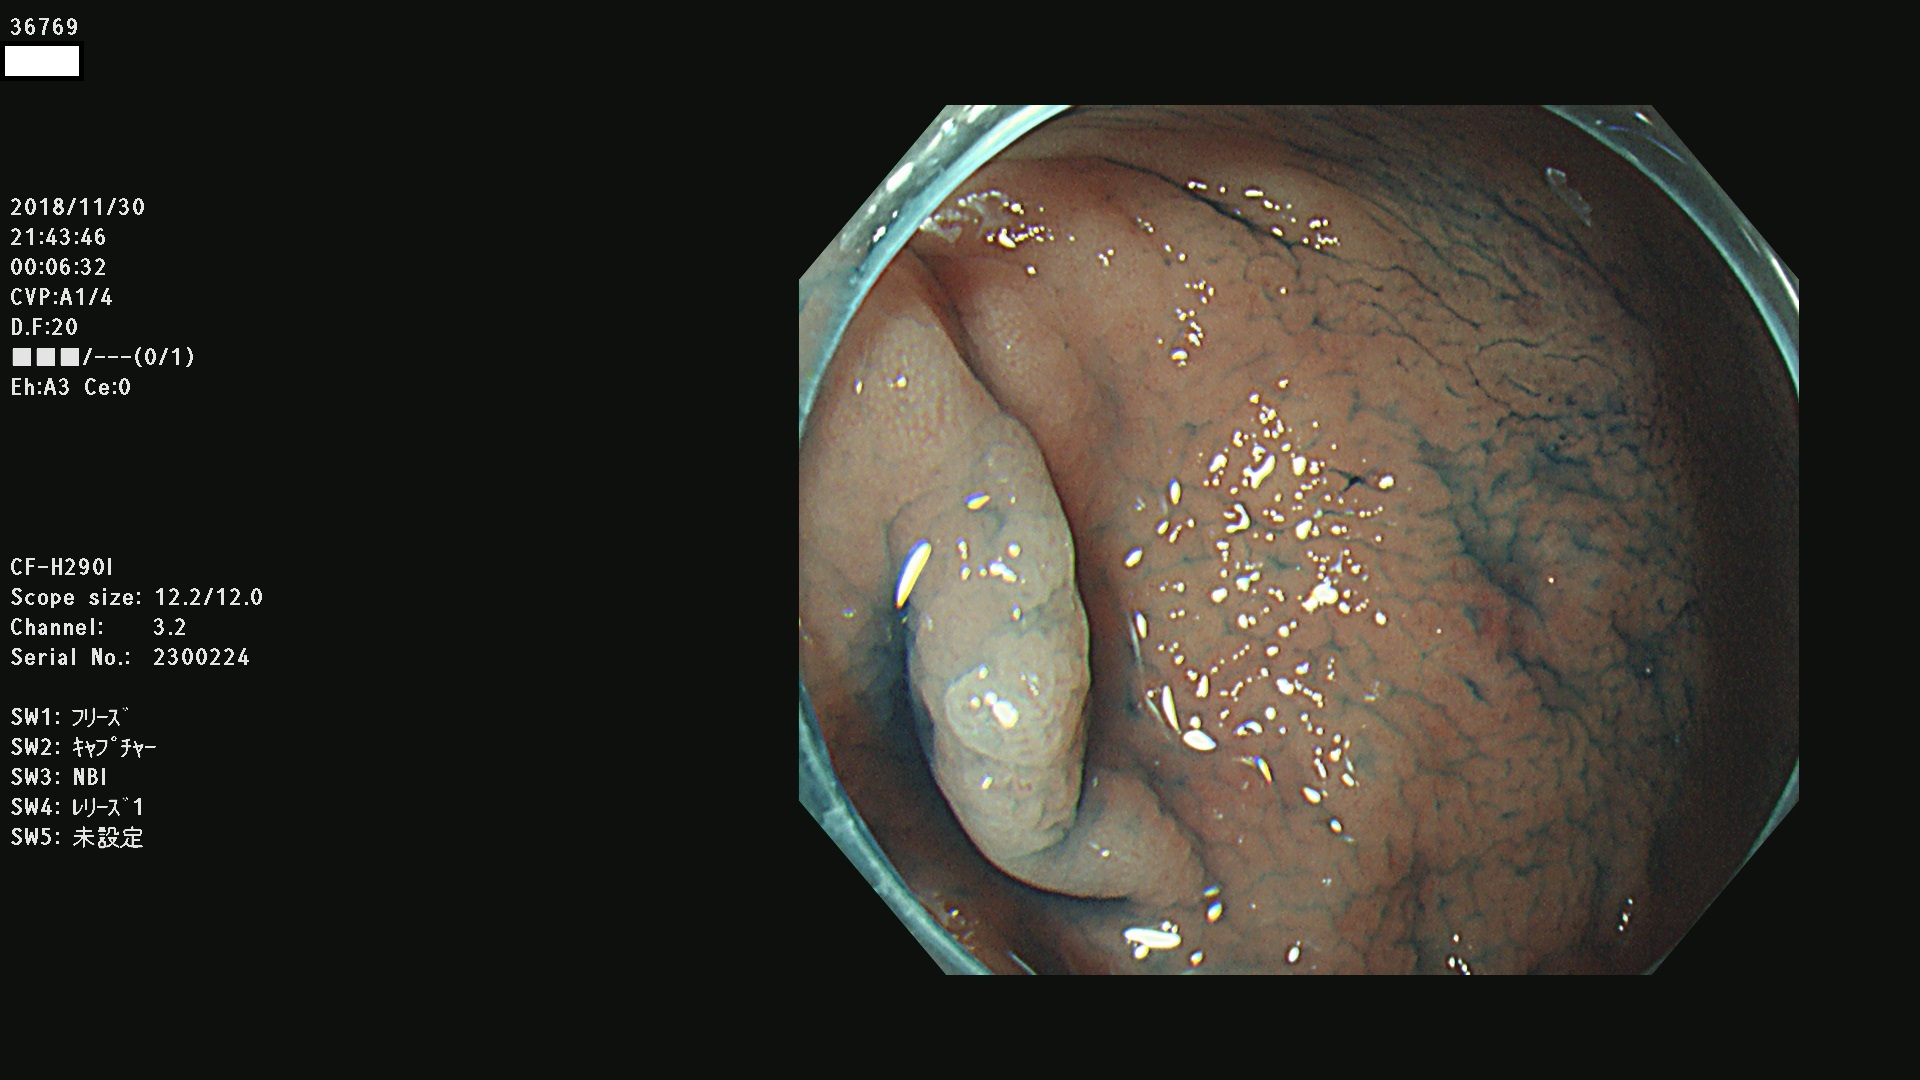

36700 36701 36702 36704 36705 36707 36708 36710 36712(SSAPのみ) 36714 36715 36716 36717 36718 36721 36723 36724 36730 36731 36732 36734 36735 36736 36738 36739 36742 36744 36745 36746 36749 36752(SSAPのみ) 36754 36756 36758 36759 36760 36731 36732 36734 36737 36738 36739 36771(SSAPのみ) 36772 36773 36774 36775 36776 36777 36780 36781 36783 36785 36786 36788 36790 36792 36794 36797 36798

発見困難で危険性の高い平坦型病変(上記100名より抽出)